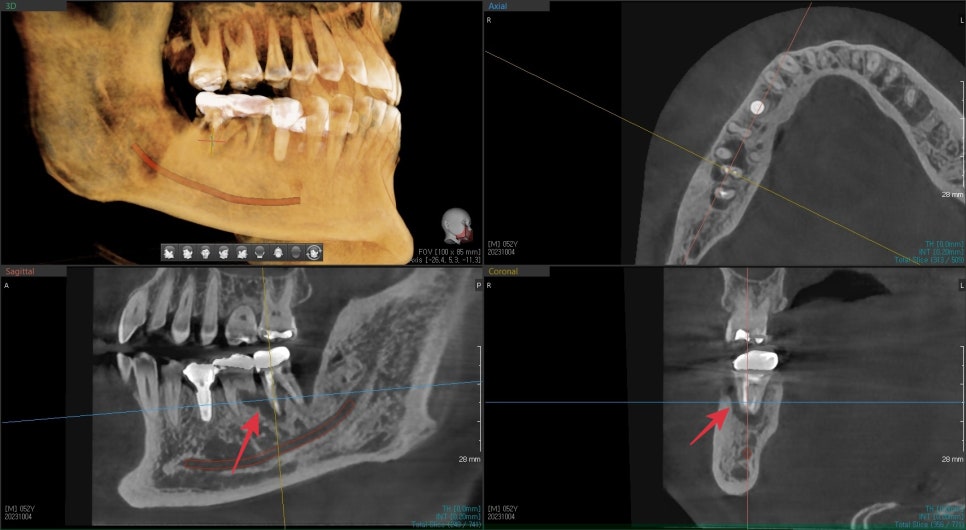

3D CT상에서 치아뿌리 주변 뼈는 염증에 의해 흡수가 되었지만

치아주변을 둘러싸는 4면의 벽은 건전한 편이라 발치 후

치조골이식술을 동반하여 즉시 임플란트 수술이 가능해보였습니다.